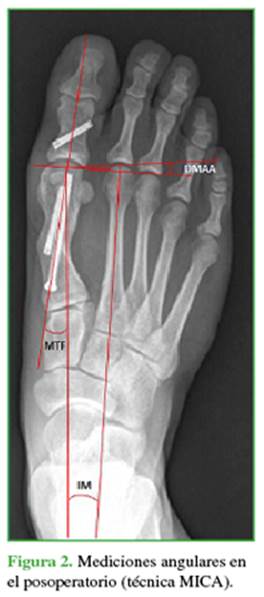

Las mediciones radiográficas después de la cirugía estuvieron a cargo de cirujanos que no habían operado al paciente (Figuras 1 y 2). De esta manera, se evaluó la pérdida o no de la corrección en ambas técnicas quirúrgicas. Todas las imágenes fueron digitales, con un programa computarizado (MB Rouler® versión 4.0), se calcularon los siguientes parámetros: a) el ángulo MTF, b) el ángulo IM usando la técnica de medición de Miller16 y c) el ángulo AMD, según la técnica mencionada por Deenik y cols.17

1)    El promedio de corrección para los ángulos MTF, IM y AMD fue de 16,83°; 1,8° y 2,06° a las 6 semanas; y de 15,8°; 1,6° y 1,98° a los 6 meses, respectivamente.

2)    La diferencia entre el ángulo IM preoperatorio y a las 6 semanas de la cirugía fue estadísticamente significativa (p <0,005), al igual que entre el preoperatorio y a los 6 meses de la cirugía (p <0,005). La relación entre la corrección IM lograda a las 6 semanas y los 6 meses no fue estadísticamente significativa (p = 0,324). Esto muestra que no hubo pérdida de corrección significativa.

3)    Las diferencias entre el ángulo MTF preoperatorio y a las 6 semanas de la cirugía, así como entre el preoperatorio y a los 6 meses de la cirugía fueron estadísticamente significativas (ambas p <0,005). La relación de corrección del ángulo MTF entre la semana 6 y el mes 6 posoperatorios fue estadísticamente significativa (p = 0,010), lo que habla de una pérdida de corrección MTF con la técnica MICA.

4)    En cuanto a la corrección del AMD, la relación entre el preoperatorio y a las 6 semanas y los 6 meses posoperatorios fue significativa en ambas mediciones (p <0,005). La pérdida de corrección entre las 6 semanas y los 6 meses de la cirugía no fue significativa (p = 0,57). No hubo pérdida de corrección.